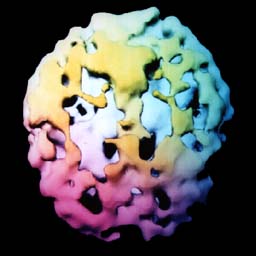

![]() 2 anos de cocaína |

O cérebro do viciado em cocaína mostra pequenos buracos múltiplos por todo o córtex cerebral. |